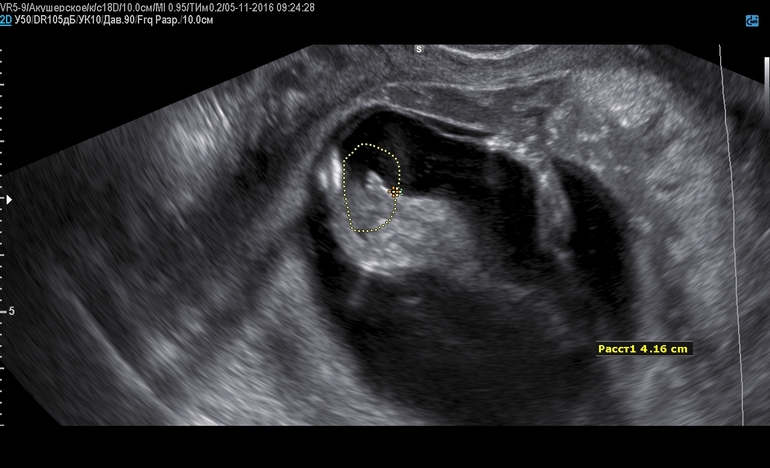

Вопросы про УЗИ, обследования и анализы: что, где, как, когда?срок 13 недель и 6 дней на узи сказали 80% что это мальчик.А вы что думаете?

На таком сроке пол еще не виден) В очень редких случаях можно что-то предположить по половом бугорку, вернее его форме, но это все равно "вилами по воде" и то, что обведено на фото - совсем не половой бугорок ;) Не торопите события)

да вот я тоже думаю что рано еще, а врач узи говорит что 80% что это мальчик и вот как раз этот бугорок мне и обвила в доказательство)))

Где то встречала, что если бугорок стоячий, то мальчик, а если лежачий, то девочка